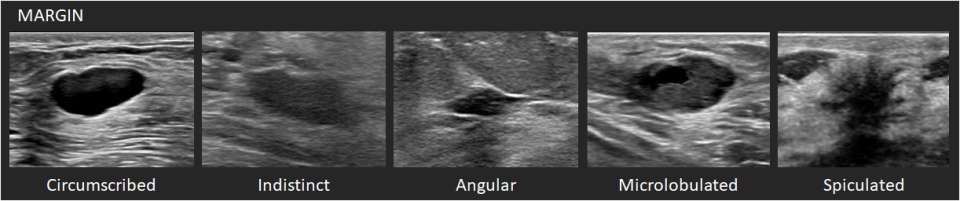

Margin: The margin is the edge or border of the lesion.

- Circumscribed: The margin is well-defined with abrupt transition between the lesion and surrounding tissue.

- Not circumscribed – If any portion or the margin is not circumscribed, the mass should be characterized as not circumscribed. The margins can be further characterized as below.

- Indistinct – No clear demarcation of the margin from the surrounding tissue.

- Angular – Some or all of the margin has sharp corners, forming acute angles.

- Microlobulated – The margin demonstrates short-cycle undulations.

- Spiculated – The margin demonstrates sharp lines radiating from the mass. This is often a sign of malignancy.